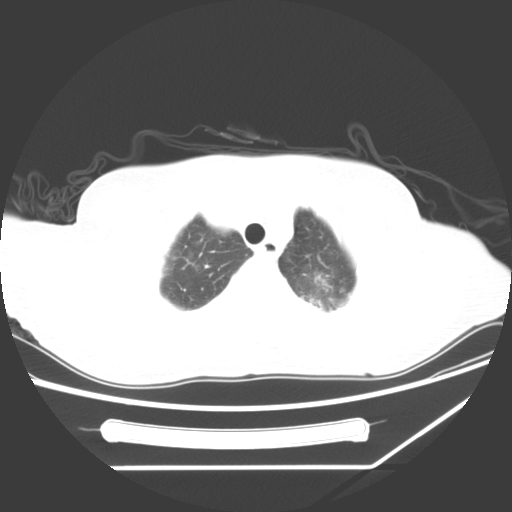

标题: CT25393:病人45岁,咳嗽,吐黄痰带血丝,发热,胸闷月余 [打印本页]

标题: CT25393:病人45岁,咳嗽,吐黄痰带血丝,发热,胸闷月余

1、左肺中央型肺癌并双肺弥漫性转移   2、双肺部感染    3、肺大泡     4、左侧胸腔积液

双侧肺弥漫性病变,可见“空泡征”及“蜂窝征”,考虑肺泡癌可能性大,左侧胸腔积液,考虑胸膜受累可能!

考虑肺泡癌,建议排除感染。

考虑肺泡癌

1)不排除肺泡癌可能。2)左侧胸腔积液。